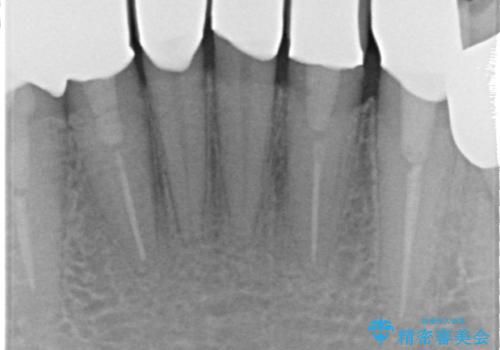

- 上下顎前歯部の見た目が気になるといらっしゃった方の症例です。

上顎は左4番から右4番までの8歯、下顎は左3番から右3番までの6歯、計14歯をオールセラミッククラウンにより補綴しました。

- オールセラミッククラウン(スタンダード)…¥100,000×14、ファイバーコア…¥20,000×6、仮歯…¥10,000×14費用は治療当時の料金となります